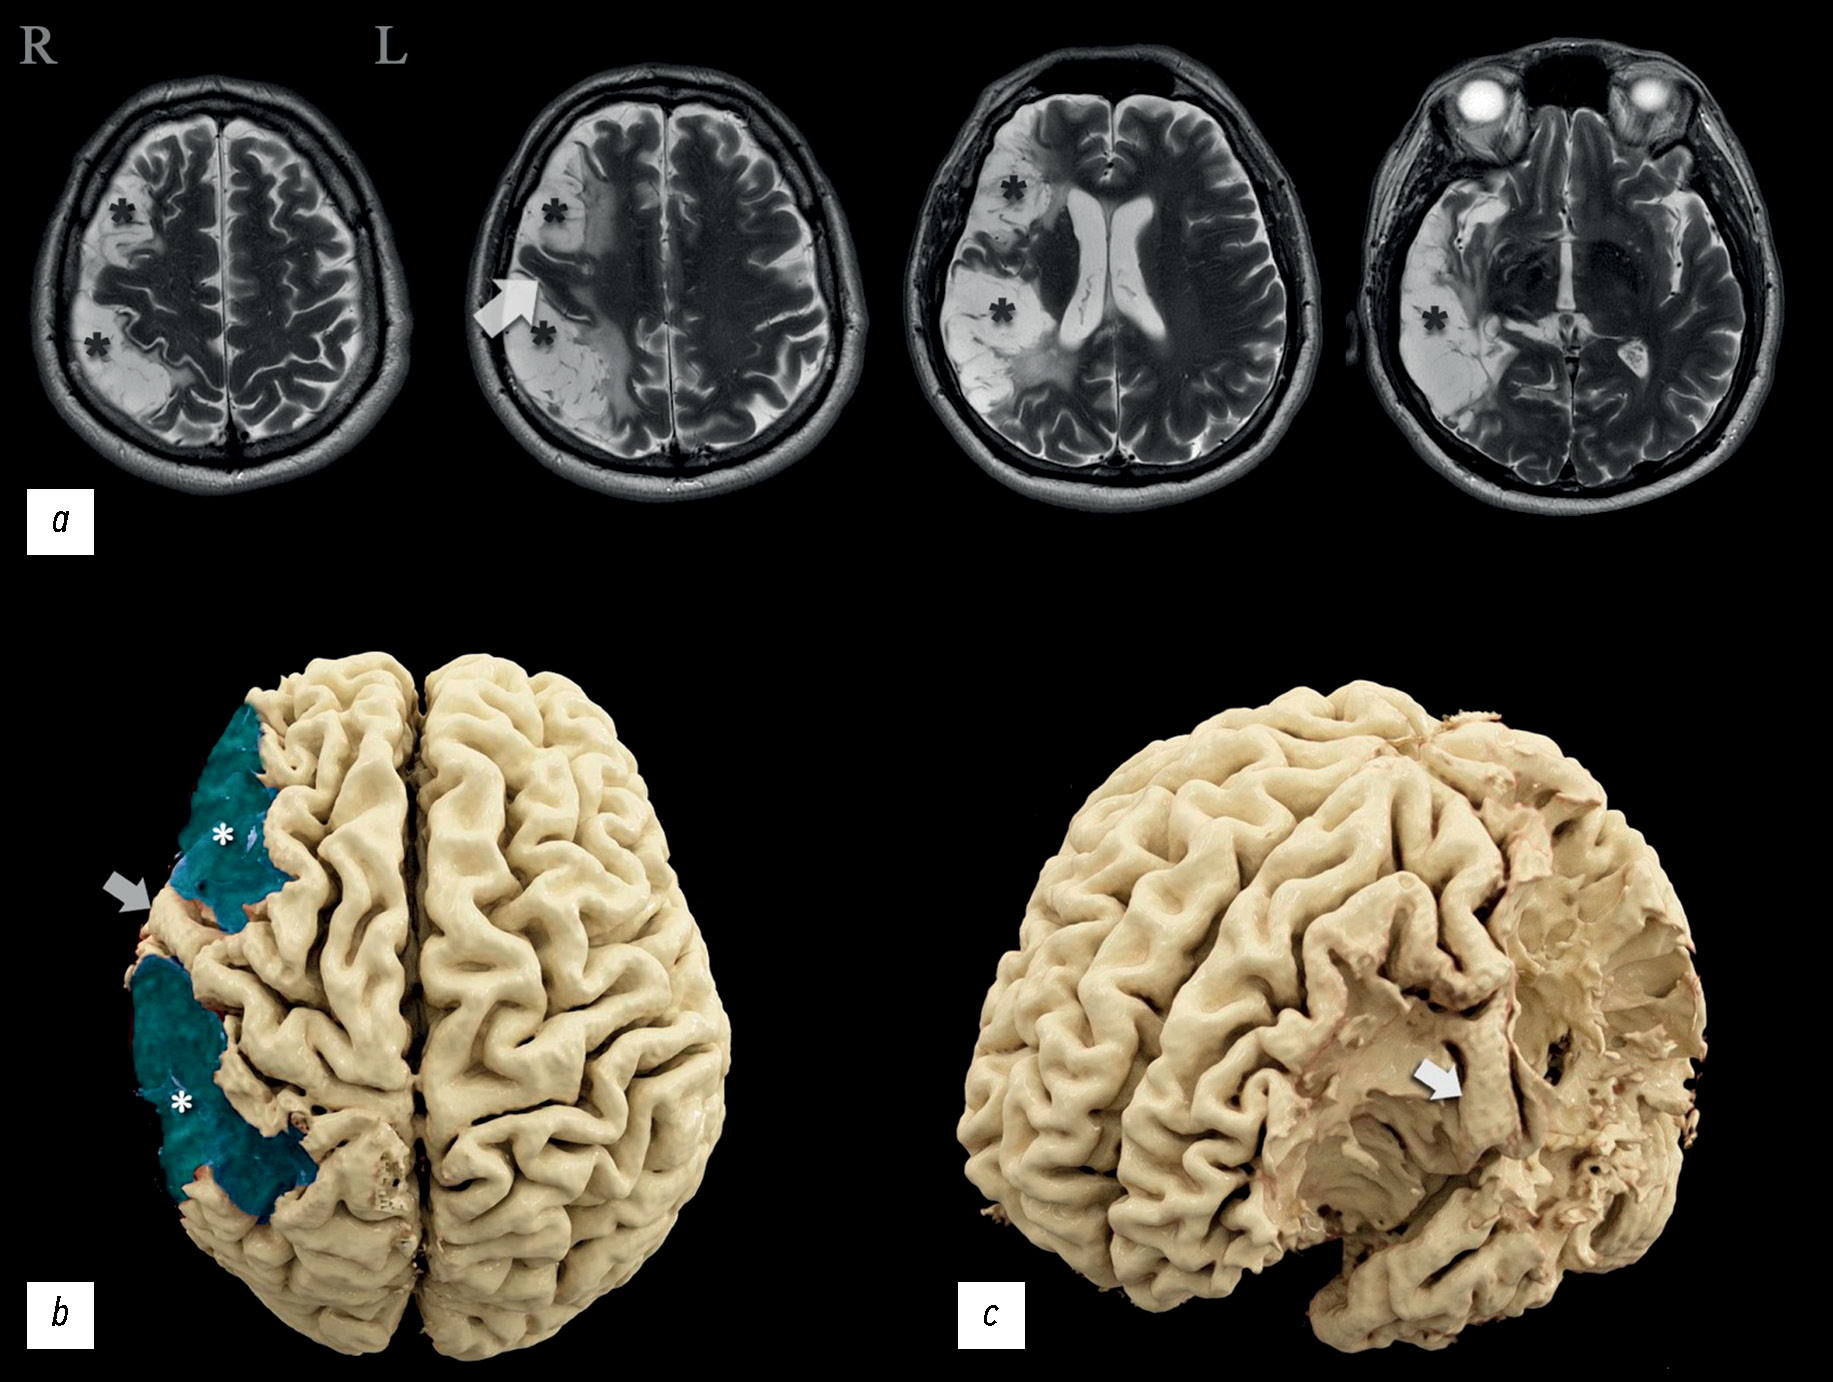

A case report of a mild neurologic deficit with extensive poststroke damage to the subdominant brain hemisphere: analysis of data obtained from magnetic resonance tractography, functional magnetic resonance imaging, and electroencephalography

Abstract

The severity of damage to different brain areas, including the cortex, can vary significantly in the associated neurologic deficit and reduction in the quality of life, often regardless of the lesion volume. The localization of the abnormalities plays a large part. Lesions of the dominant and subdominant hemispheres can differ greatly in both clinical features and effects on the patient’s quality of life. In this case report, a patient admitted for rehabilitation after two ischemic strokes underwent neurological and neuropsychological examination, complex instrumental diagnostics using electroencephalography, magnetic resonance imaging, computed tomography perfusion, magnetic resonance tractography, and functional magnetic resonance imaging. The patient had minimal left-sided hemiparesis, impaired regulation of voluntary activity, mild decrease in neurodynamic indicators, mildly impaired concentration, and a critical view of his condition. Neuroimaging findings demonstrated extensive postinfarction damage to the right subdominant hemisphere of the brain in the middle cerebral artery circulation. A nonconformity between the brain damage volume and the severity of its clinical signs was observed. Based on functional examination data, the dominant hemisphere was determined, and restructuring the functional centers was suggested. This clinical case was compared with similar ones, and their relationship with the data was analyzed. Information that expands the knowledge of the topography of the altered zones involved in motor and speech functions and the ability to perform arithmetic counting was obtained.

601-612